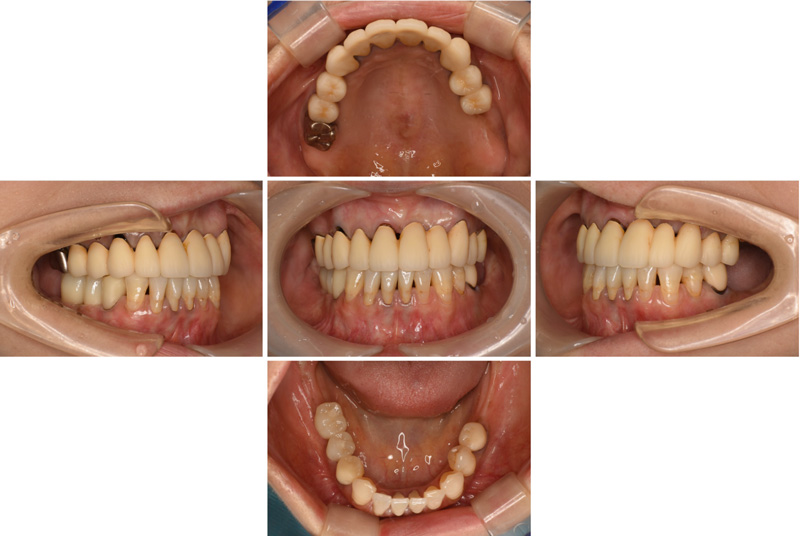

57歳男性

治療前

治療後

| 施術名 | インプラント治療 |

| 施術の説明 | インプラント治療とは、歯を抜いた所にチタン製の人工歯根を埋入し、新しく歯を入れる方法です。 |

| 施術の副作用 (リスク) | 腫れや疼痛を感じる、違和感を感じるなどの症状を生じることがあります。 |

| 施術の価格 | 53万円~+消費税 |